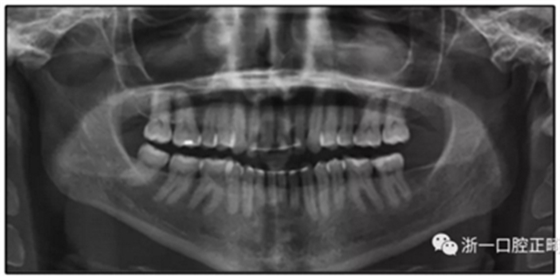

患者是一名39歲的白人婦女,病史不明。她主訴是她的右側(cè)顳下關(guān)節(jié)有不適癥狀,并希望改善她的笑容。她有一個(gè)對(duì)稱的臉型和一個(gè)II類2分類的微笑。她的側(cè)貌是凸的,90°的鼻唇角和骨性下頜骨發(fā)育不足??趦?nèi),上頜中線與面部重合,但下頜中線向右側(cè)偏移5mm;存在6mm的深覆蓋。她的兩側(cè)都是I類磨牙關(guān)系,左側(cè)是I類尖牙關(guān)系,右側(cè)是完全的II類尖牙關(guān)系。下頜右側(cè)第二前磨牙先天性缺失(圖1和圖2)。最初的全景片顯示了足夠的骨質(zhì)水平和全部的第三磨牙(圖3)。治療前的頭影測(cè)量片片和相應(yīng)的頭影測(cè)量圖(圖3)證實(shí)ANB為7°,Wits評(píng)估為6 mm的骨性II類錯(cuò)合(表)。上頜切牙相對(duì)與面部和顱底的位置很好。下頜切牙前傾。診斷為II類2分類錯(cuò)合畸形,伴有骨性下頜發(fā)育不足,右側(cè)顳下頜關(guān)節(jié)癥狀,下頜中線向右側(cè)偏移5mm,先天性右下第二前磨牙缺失。

圖3. 治療前頭影側(cè)位片,頭影測(cè)量描跡圖和全口X光片